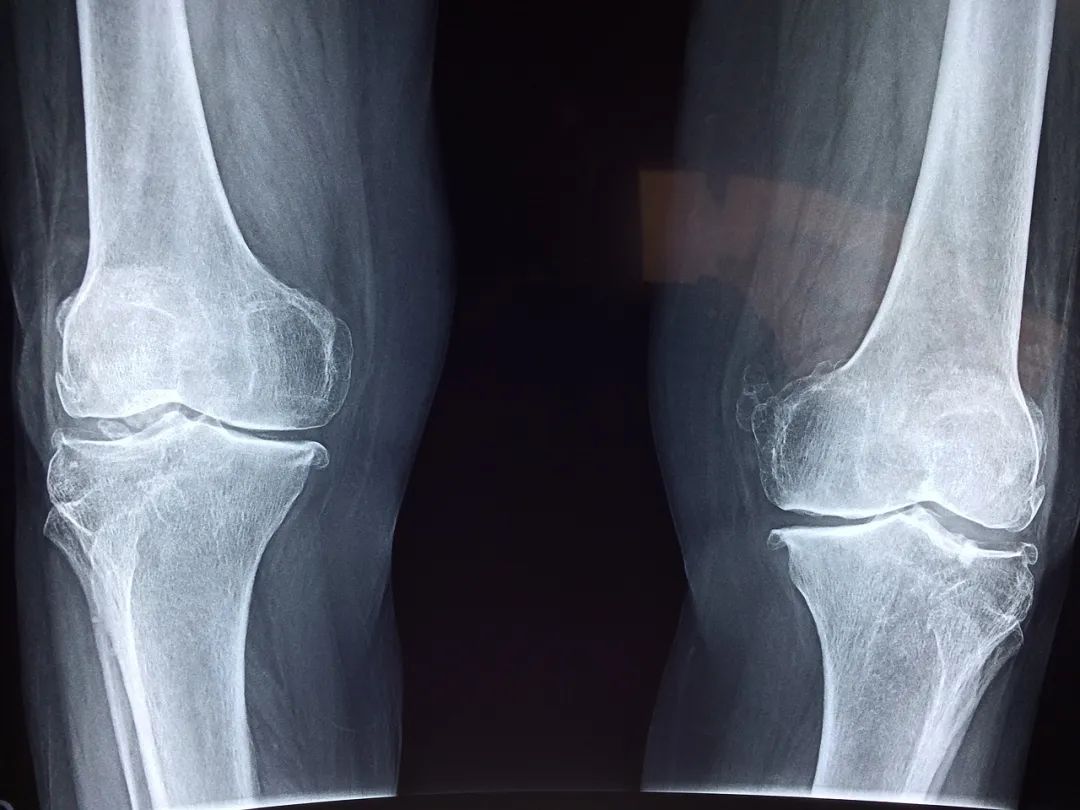

膝關(guan) 節出現這些症狀,可能已經提示關(guan) 節受損

有的時候膝關(guan) 節會(hui) 出現一些響聲,很清脆的一次彈響,不伴有疼痛的,可能是一些生理性的彈響,比如說我們(men) 滑膜增生等。如果退行性的骨關(guan) 節病、關(guan) 節炎,它的響聲是非常有特征性的,就像冬天你去握一把雪,雪球就發出咯吱咯吱的聲音,這種握雪感是非常典型的骨關(guan) 節炎的一個(ge) 表現,叫作骨摩擦音。

3. 膝關(guan) 節出現了這些症狀可能已經提示關(guan) 節受損:疼:膝關(guan) 節內(nei) 側(ce) 的間隙疼,可能半月板或者骨關(guan) 節炎出現問題;響聲:骨關(guan) 節病、關(guan) 節炎會(hui) 出現骨摩擦音。